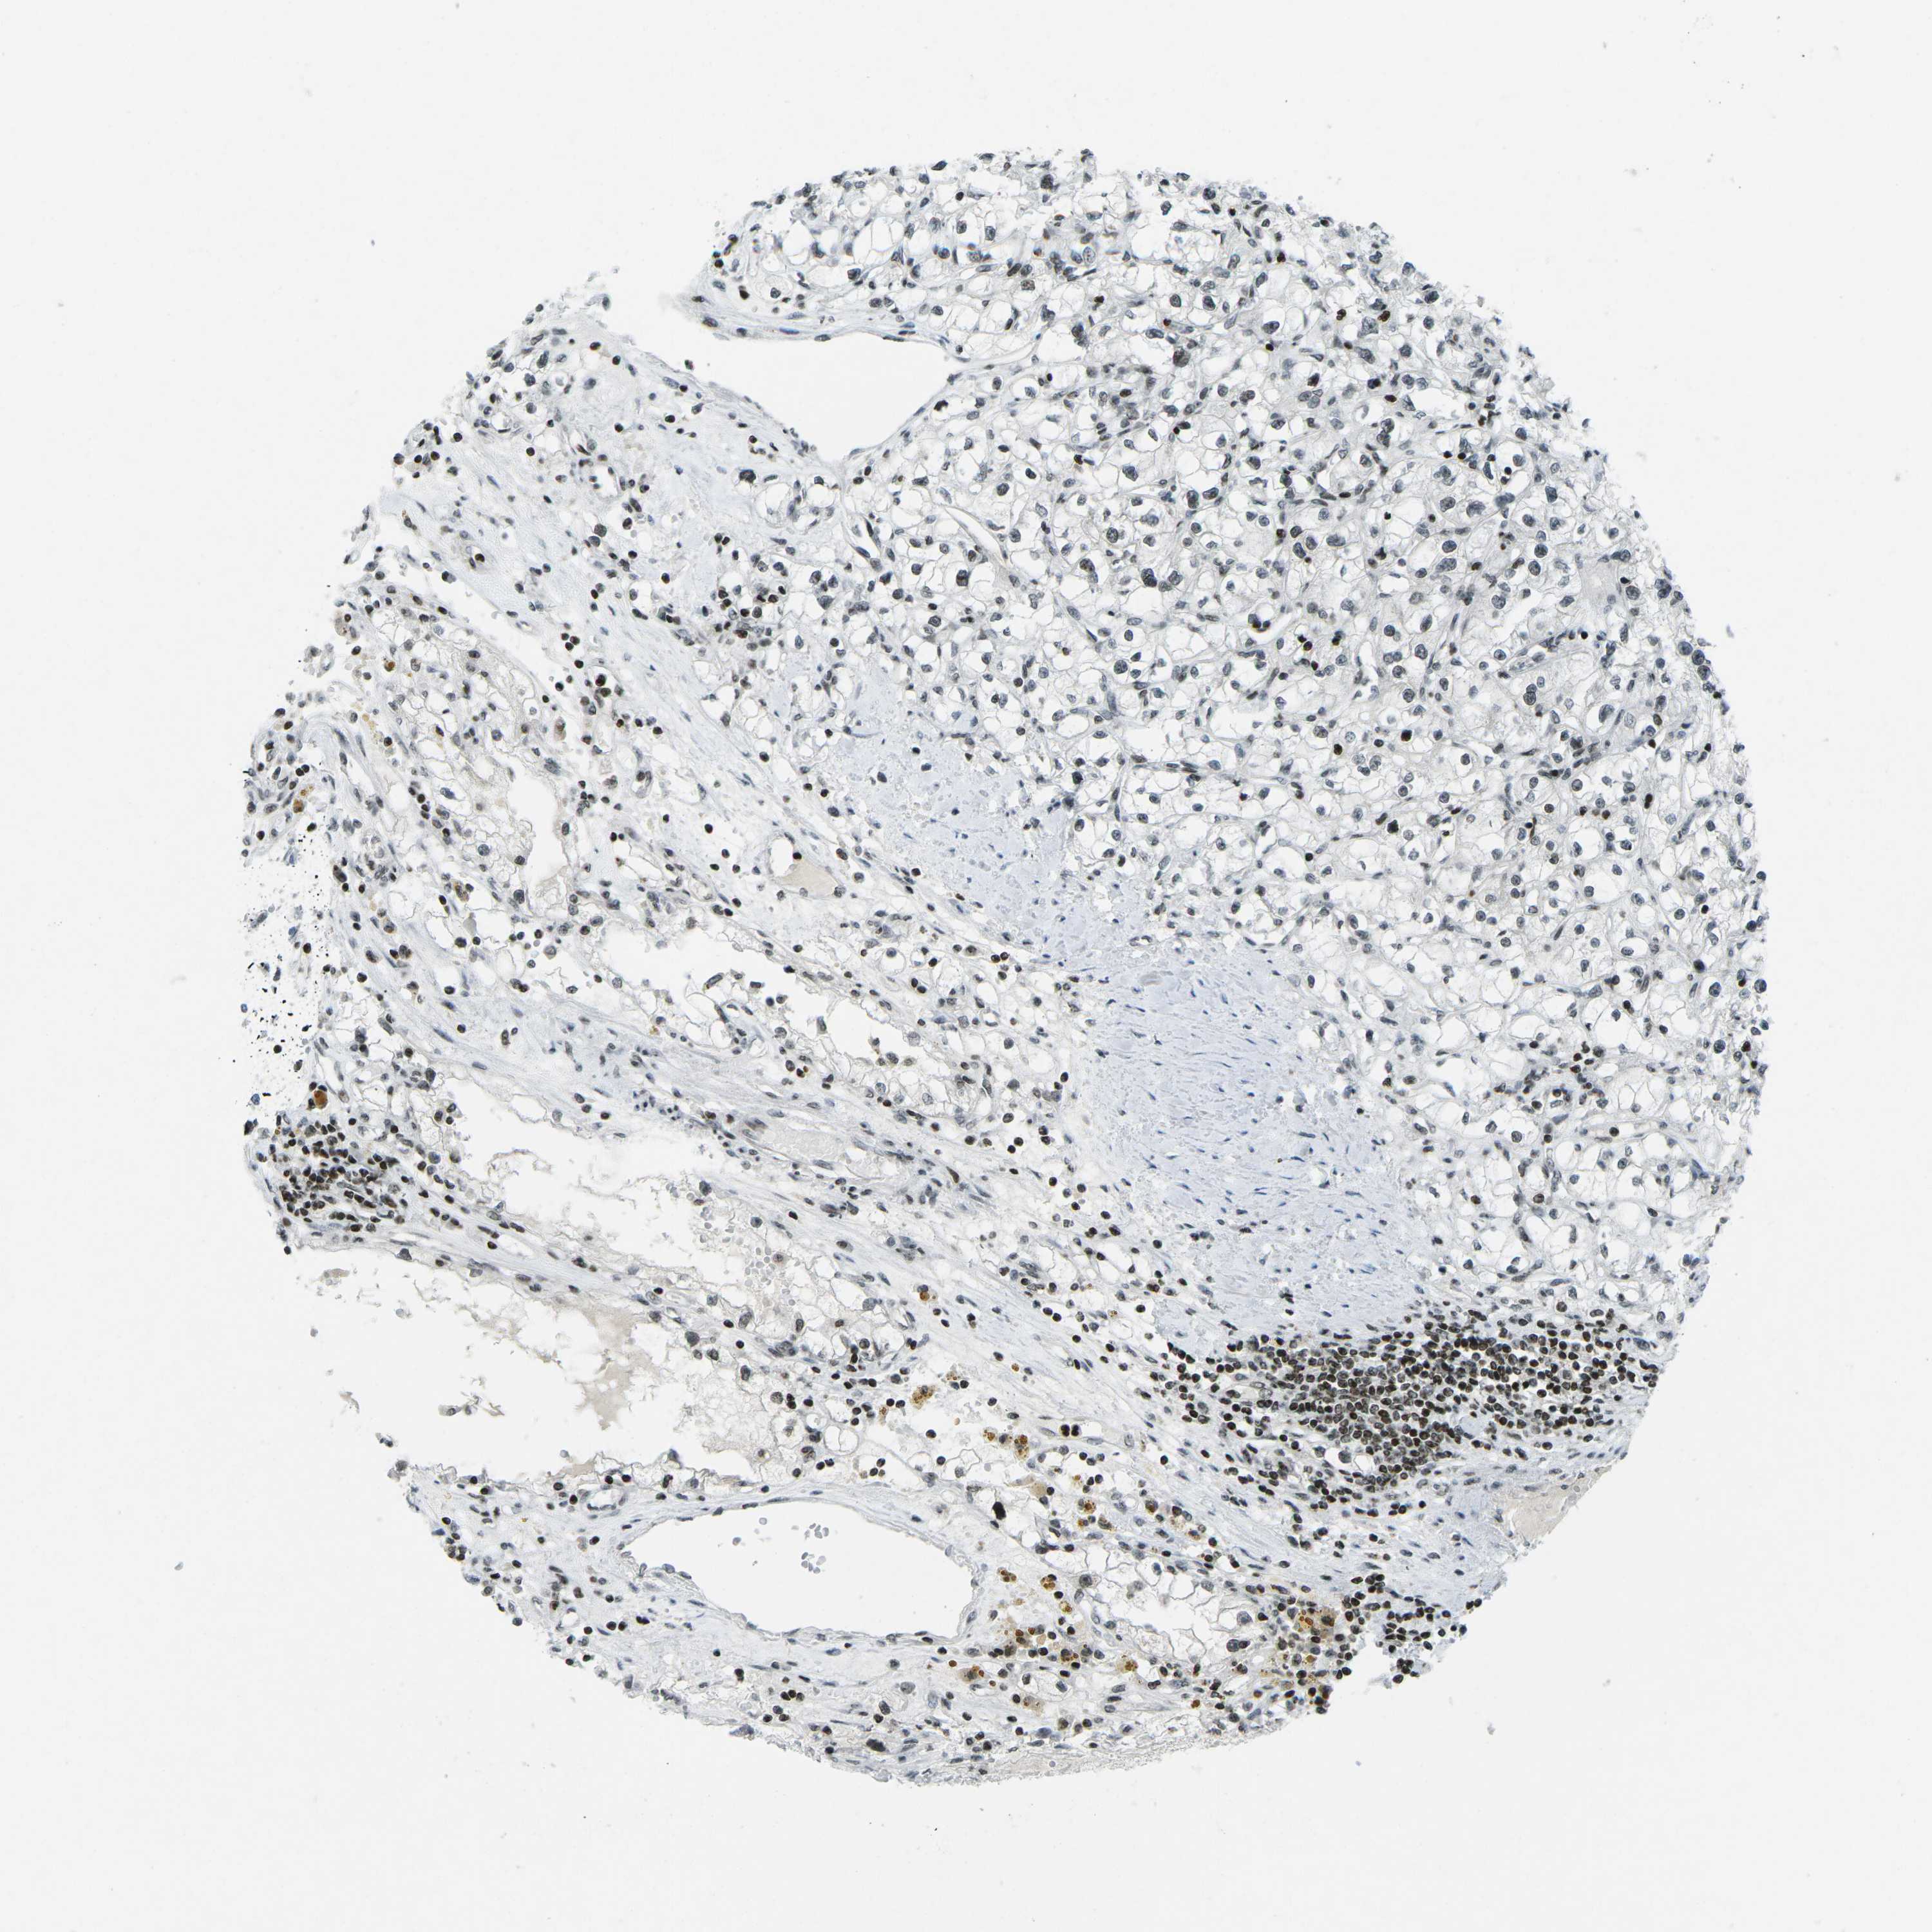

KIDNEY RENAL PAPILLARY CELL CARCINOMA (TCGA) - Interactive survival scatter ploti

The Survival Scatter plot shows the clinical status (i.e. dead or alive) for all individuals in the patient cohort, based on the same data that underlies the corresponding Kaplan-Meier plots. Patients that are alive at last time for follow-up are shown in blue and patients who have died during the study are shown in red.

The x-axis shows the expression levels (FPKM) of the investigated gene in the tumor tissue at the time of diagnosis. The y-axis shows the follow-up time after diagnosis (years). Both axes are complimented with kernel density curves demonstrating the data density over the axes. The top density plot shows the expression levels (FPKM) distribution among dead (red) and alive patients (blue). The right density plot shows the data density of the survived years of dead patients with high and low expression levels respectively, stratified using the cutoff indicated by the vertical dashed line through the Survival Scatter plot. This cutoff is automatically defined based on the FPKM cutoff that minimizes the p-score. The cutoff can be changed by dragging the vertical line or by entering a cutoff value in the square labeled "Current cut-off".

Under the Survival Scatter plot the p-score landscape (black curve; left axis) is shown together with dead median separation (red curve; right axis). Dead median separation is the difference in median mRNA expression between patients who have died with high and low expression, respectively. It is calculated as follows: median FPKM expression of dead patients with high expression - median FPKM expression of dead patients with low expression. This is intended to aid the user in visually exploring custom cutoffs and the associated p-scores and dead median separation.

Individual patient data is displayed and can be filtered by clicking on one or more of the category buttons on the top of the page. Categories describing expression level and patient information include: high, low, alive, dead, female, male and tumor stages. The scale of the x-axis can be toggled between linear and log-scale by clicking on the "x log" button. Mouse-over function shows TCGA ID, patient information and mRNA expression (FPKM) for each patient.

& Survival analysisi

Kaplan-Meier plots summarize results from analysis of correlation between mRNA expression level and patient survival. Patients were divided based on level of expression into one of the two groups "low" (under cut off) or "high" (over cut off). X-axis shows time for survival (years) and y-axis shows the probability of survival, where 1.0 corresponds to 100 percent.

EME1 is not prognostic in Kidney Renal Papillary Cell Carcinoma (TCGA)